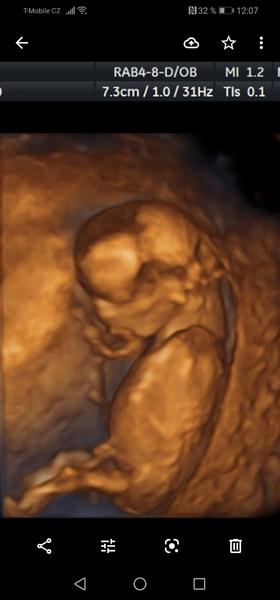

@kajda3 mám ještě tyhle. Ta jedna jsou vyloženě nožičky a bříško, je jakoby cele k nám.

@kajda3 ještě možná tuhle, tady přirození trochu je vidět, po přiblížení. Prý ty pysky jsou taky hodně velké. Prostě nevím. 😥